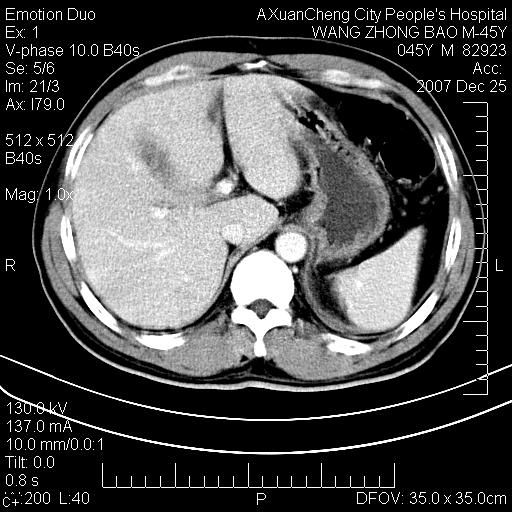

以下是引用qiuleiyu在2007-12-25 18:14:00的发言:[br]胰腺增大,周边渗出改变,肾前筋膜明显增厚,示少量积液.胆囊壁毛糙,周边少许渗出,胆总管壁厚,异常强化,然扩张不明显.结合病程急短;考虑;胆管炎,胆囊炎,胆源性胰腺炎可能大,请结合实验室检查及随访.

以下是引用lisihao在2007-12-25 14:23:00的发言:[br]急性水肿型胰腺炎[br]依据:1、胰腺弥漫性肿大,边缘稍毛糙;[br] 2、双侧肾周筋膜增厚,尤以左侧为甚(重要征象)[br] 3、双侧后胸膜增厚(刺激性炎症);[br] 4、结合病史,查血尿淀粉酶应该可以确诊。